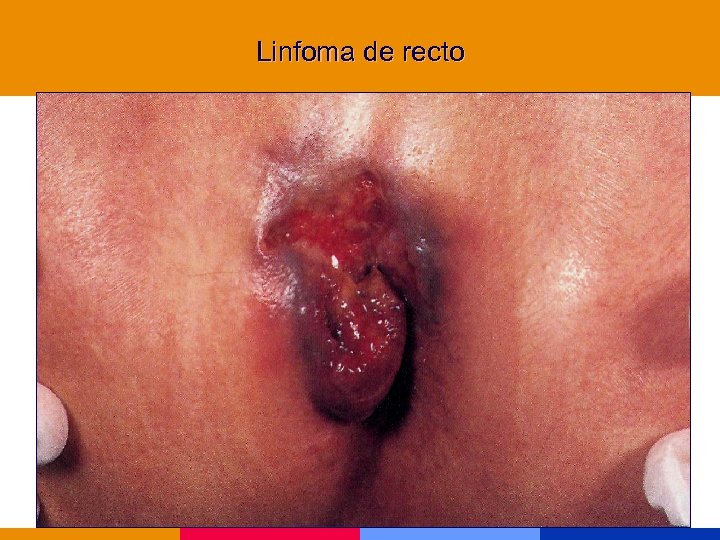

Neoplasias marcadoras § Cáncer de cuello uterino, invasivo § Sarcoma de Kaposi § Linofoma no Hodking, primario de SNC Incremento de otras neoplasias: pulmón, seminoma, melanoma, otras

Neoplasias marcadoras § Cáncer de cuello uterino, invasivo § Sarcoma de Kaposi § Linofoma no Hodking, primario de SNC Incremento de otras neoplasias: pulmón, seminoma, melanoma, otras

Linfoma de recto

Linfoma de recto